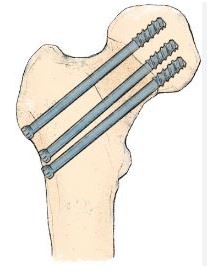

Për frakturat e qafës së femurit

Fiksim me vida / vida kanjuluara

- Kryesisht tek pacientët e rinj

- Ruhet koka e femurit